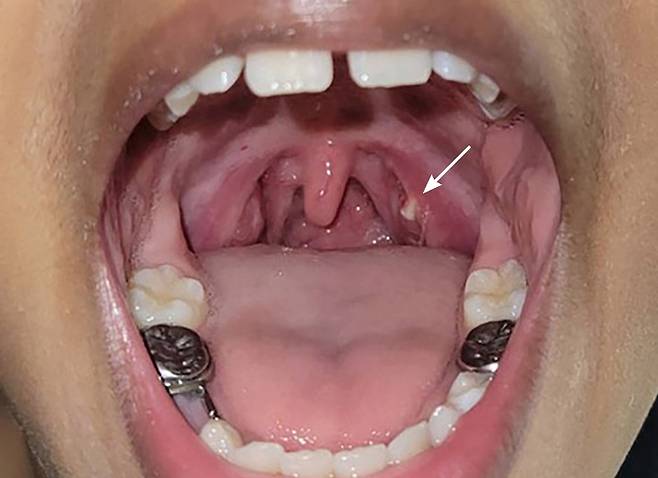

편도결석은 말 그대로 편도에 결석이 생긴 것이다. 편도는 입을 벌렸을 때 늘어진 목젖 양 옆 주름진 벽이다. 코와 입으로 들어오는 세균을 방어하는 면역기관 역할을 한다. 보통 편도라 통칭하지만, 세부적으로는 혀 안쪽에 위치한 편도와 목젖 양 옆에 튀어나온 구개편도, 입천장의 인두편도로 나눈다. 편도에는 '편도음와'라고 불리는 작고 깊은 구멍이 있는데, 우리가 음식을 삼킬 때 이 구멍 안으로 찌꺼기가 낄 수 있다. 이로 인해 찌꺼기가 쌓이면서 결석을 형성한다.

편도결석은 다른 결석보다 말랑말랑한 편이다. 보통 0.5mm 정도 크기이며, 연한 노란색의 밥풀 모양이다. 간혹 1.5cm가 넘는 거대결석도 있다.

바깥쪽에 있는 편도결석은 입을 '아'하고 벌렸을 때 흰색 이물질이 육안으로도 쉽게 보인다. 그러다 보니 이것을 젓가락이나 면봉으로 빼내려고 하는 사람도 있다. 하지만 이는 금물이다. 결석을 정확하고 깔끔하게 제거하기는 쉽지 않으면서, 꺼내려는 과정에서 구강 내부나 편도가 긁혀 염증을 일으킬 수도 있다. 이상이 느껴지면 이비인후과를 찾아가 구강검진과 인후두내시경 검사로 결석인지 확인하는 게 안전하다. 편도결석으로 확인되면 병원에서는 후두내시경을 보면서 기계로 결석을 빨아들이거나 결석을 압출하는 치료를 한다. 입안 깊숙하게 기기를 넣을 경우 구역질이 날 수 있기 때문에 국소마취를 하기도 한다. 결석을 제거한 후에도 계속 생긴다면 편도를 잘라내는 수술을 고려할 수 있다.